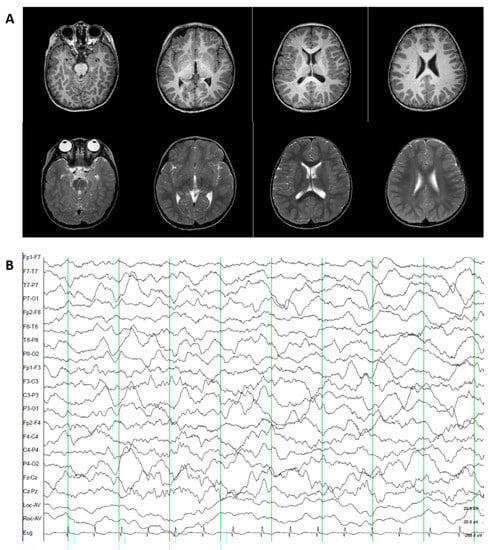

3.1.2. Patient 2. Autosomal Recessive Dopa-Responsive Dystonia (OMIM 605407)

3.2.2. Patient 2. Autosomal Recessive Dopa-Responsive Dystonia (OMIM 605407)

3.3.2. Patient 2. Autosomal Recessive Dopa-Responsive Dystonia (OMIM 605407)